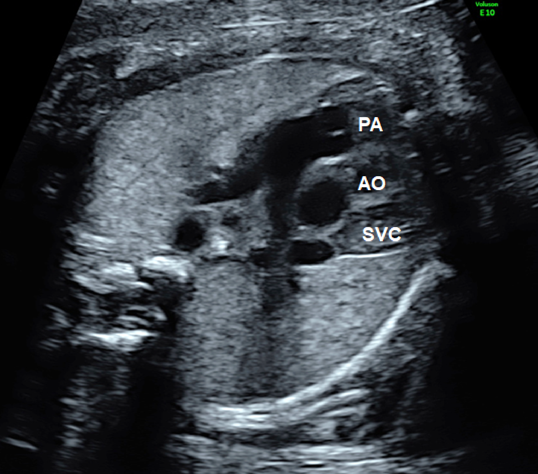

Tilting the probe toward the head of the fetus during the 4CV gives a view of the ventricular outflow tracts (Fig. 7). The left ventricular outflow tract (the aorta does not branch immediately after originating from the ventricle) is visualized first (Fig. 10), then the right ventricular outflow tract (the pulmonary artery branches immediately after originating from the ventricle) with further tilting (Fig. 11). The whole picture of the major vessels and their connections to the ventricles can be seen in the long-axis view. The normal features of the outflow tracts are; 1) a couple of major vessels present with the pulmonary arterial trunk greater than the aorta, 2) these vessels crossing each other spatially, 3) the vessels arising one each from the ventricles, and 4) the interventricular septum and the anterior wall of the aorta being a continuum.

Another method is to move the probe in parallel to the 4CV towards the cranial direction (Fig. 8). The 3VV is obtained with the horizontal and cranial shift of the probe. This provides a picture in which the pulmonary arterial trunk and the aorta are seen at once on a single cross-section so that their positions and sizes can be analyzed. In a normal instance, the pulmonary arterial trunk, the aorta, and the superior vena cava appear in a straight line, with the pulmonary arterial trunk being greatest and the superior vena cava smallest (Fig. 9).